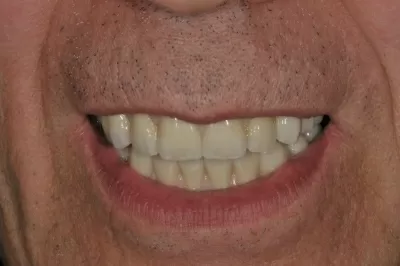

Галерея